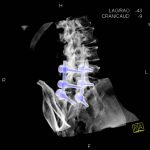

- Diagnosticul fracturilor:

-

- Unice

- Multiple

- Cu înfundare

- Complexe cranio-sinusale

- Complexe cranio-etmoidale

- Complexe cranio-orbitare

- Complexe cranio-faciale